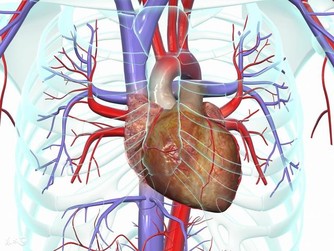

1 、心火

心火是非常容易產生的,一般情況下,當一個人長時間出現思慮過多的時候,就很容易耗傷心陰,從而出現心火旺盛的情況,常見的臨床表現有舌尖泛紅,小便黃赤,這是心火的典型表現。